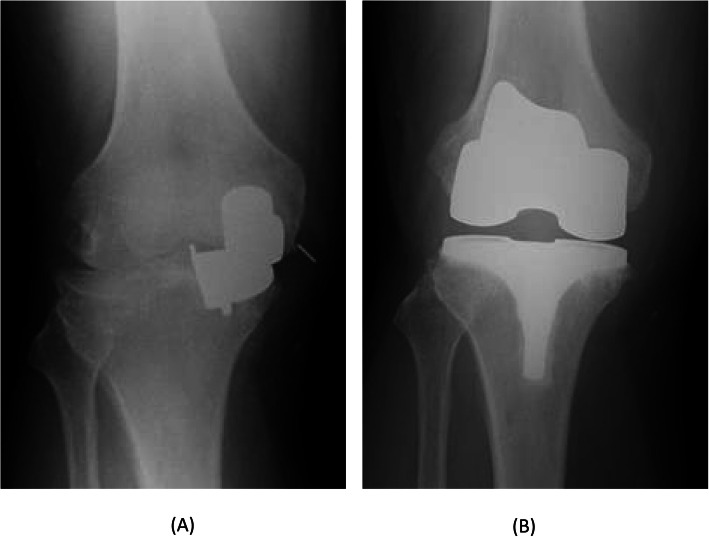

Fig. 8.

Radiographs 5 months after the additional surgery shows bearing re-dislocation (a). Radiographs after the revision to total knee arthroplasty (b)

The second case was a 52-year-old man (body weight, 101 kg; height, 179 cm; and BMI, 31.5 kg/m2) with anteromedial osteoarthritis of the right knee. The preoperative Knee Society and Knee Society Functional Scores were 57 and 60 points, respectively. The ROM of the left knee was 125° flexion and 5° extension. The surgical technique used for Case 2 was the same as that used for Case 1. The patient had a good bone quality. Therefore, a medium-sized cementless femoral component and D-sized cementless tibial component with a 5-mm thick meniscal bearing were implanted. Intraoperatively, we confirmed the same gap balance between knee flexion and extension, and the anterior cruciate ligament was well-tensioned and covered with synovial membrane. There was no abnormal movement of the meniscal bearing or signs of bearing dislocation. The postoperative radiographs showed appropriate implantation (Fig. 5). Immediately after the operation, the pain disappeared, and he resumed playing Judo 6 weeks postoperatively. Seven months postoperatively, he had sudden and severe knee pain when he tried to ride a bicycle. The meniscal bearing was anteriorly dislocated as shown on the radiographic images (Fig. 6). During the additional surgery, although the tibial component slightly subsided anteriorly, there was no loosening of the tibial component. We did not check the fixation stability of the femoral component because we did not expect loosening of the femoral component. We changed the mobile bearing from 5- to 9-mm thickness and confirmed no signs of bearing dislocation intraoperatively. We observed femoral migration and radiolucent zone around the femoral pegs from the radiographic images taken postoperatively (Fig. 7). Five months after the additional surgery, he experienced another bearing anterior dislocation, so we performed revision surgery (Fig. 8a). During the surgery, the femoral component subsided approximately up to 4 mm and was loose enough to be easily retrieved using an elevator. We retrieved the components and revised to total knee arthroplasty (Journey II BCS. Smith and Nephew, Memphis, TN, USA; Fig. 8b).